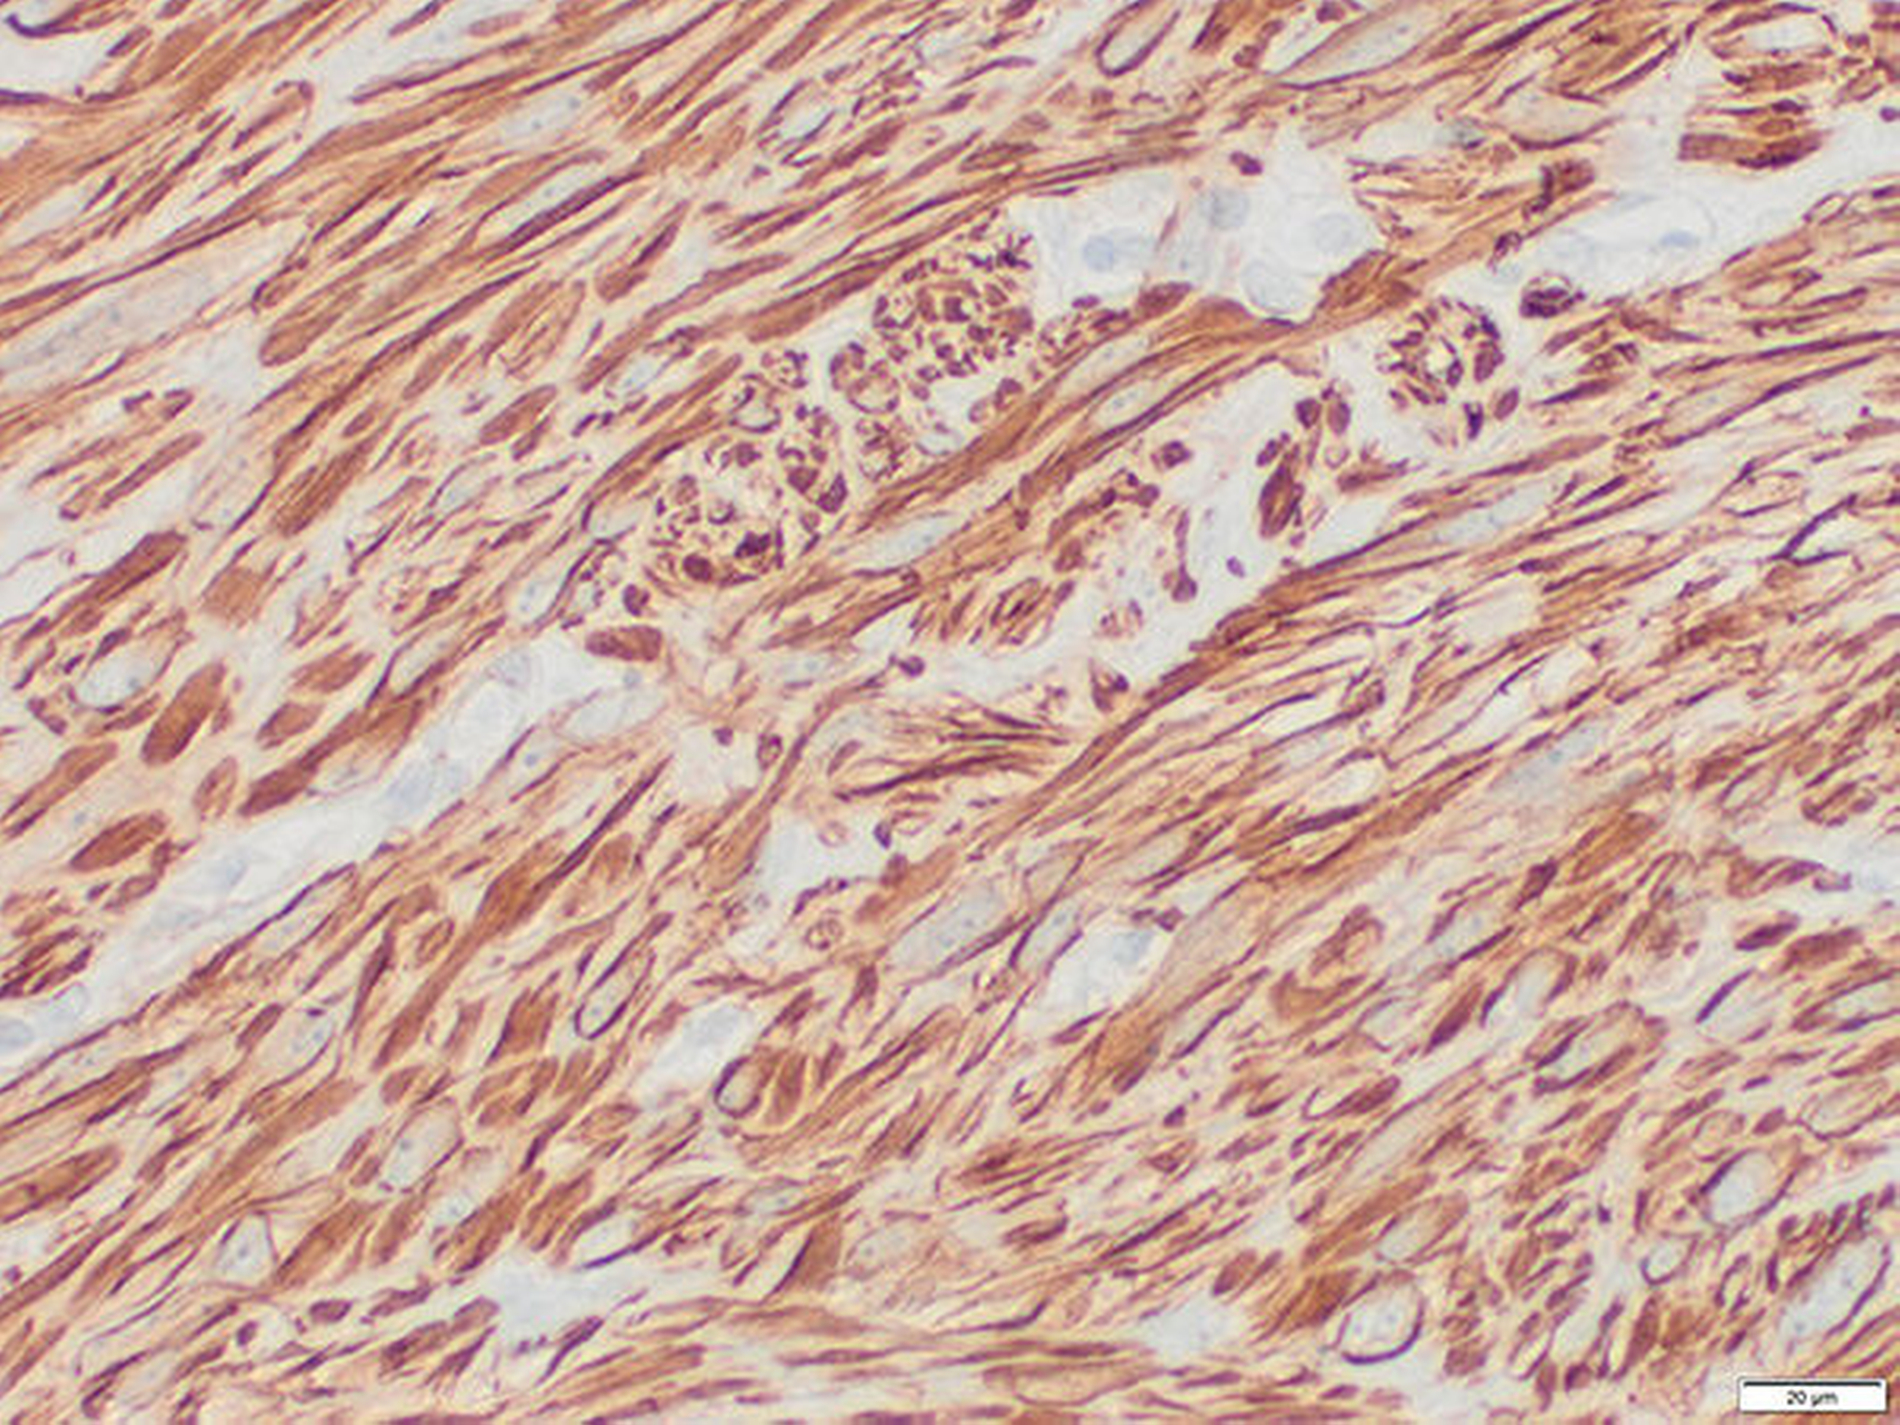

Zur Kontrolle erfolgten MRT-Kontrollaufnahmen des ganzen Körpers in einem dreimonatigen Abstand. Bei Vorstellung in unserer Klinik zeigte sich abgesehen von einem diskreten Bulbushochstand und Exophthalmus rechts ein unauffälliger klinischer Befund. Im MRT zeigte sich eine intraorbitale Raumforderung (Abbildung 1). Die histologische Untersuchung bestätigte den Verdacht auf eine Neumanifestation des Leiomyosarkoms (Abbildungen 2, 3).